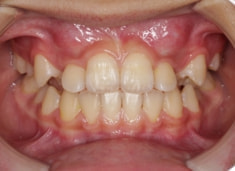

小児期ケース:反対咬合+上顎両側3番埋伏歯

(受け口+3番目の永久歯が左右両方とも埋まってしまい、はえてこない)

治療前